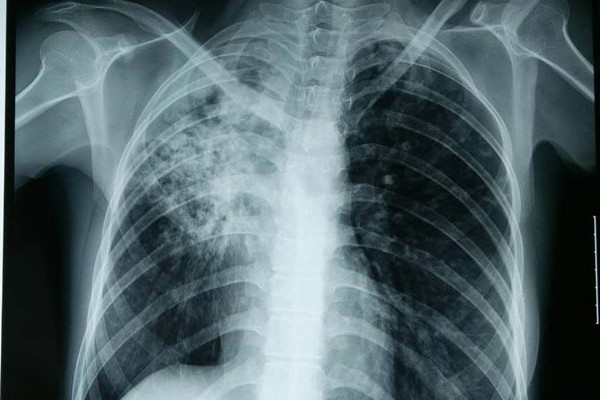

结核性胸膜炎是一种由结核杆菌入侵感染所引起的胸膜炎症,其临床表现为全身乏力、发热、盗汗、胸痛、呼吸困难及干咳等,那么患上结核性胸膜炎能治好吗?在小编看来选择正确的治疗方法,做好综合护理,治愈的希望是非常大的。

目前临床上的治疗方法优先是抗结核药物治疗,如果有胸腔积液且量大就会选择胸腔抽液治疗或者手术干预。不过选择精准治疗的方法外,加强护理也非常重要,下面我们就简单来看下。